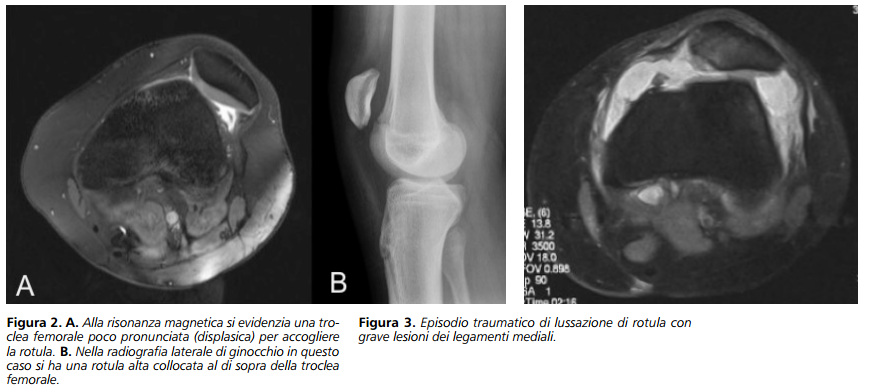

Nelle forme congenite esistono delle “anomalie” ossee o legamentose che possono causare la lussazione come ad esempio una rotula eccessivamente alta, un tendine rotuleo eccessivamente lateralizzato, una conformazione troppo “piatta” e poco contenitiva della troclea femorale o una insufficienza dei legamenti mediali che mantengono la rotula nella loro sede (Figura 2 A-B).

Le forme traumatiche invece avvengono generalmente in assenza di fattori predisponenti in cui il trauma rappresenta il principale determinante della lussazione della rotula. Si tratta frequentemente di un trauma distorsivo del ginocchio o di un trauma diretto sulla regione mediale della rotula che determina la sua lussazione verso l’esterno (Figura 3).